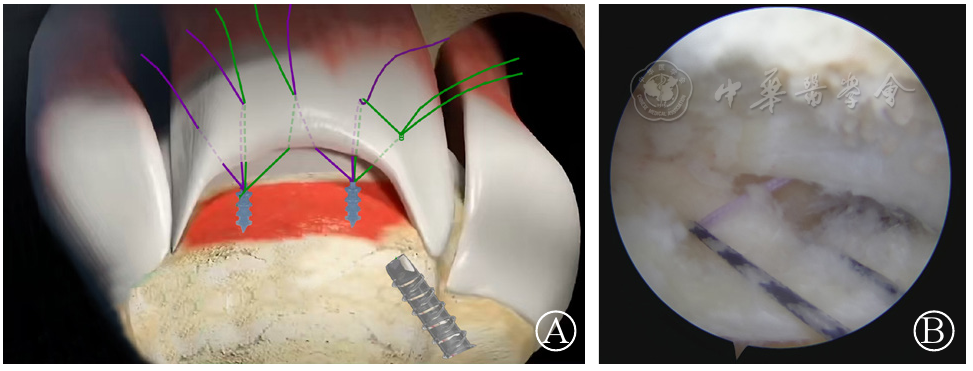

图3 缝合线绕线 图A:动画示意图;图B:手术镜下操作过程:将内排锚钉同一颜色缝线(绿色)抓出入路套管,在打结前,通过抓线钳将相伴缝线(紫色)与欲打结的缝线(绿色)交锁缠绕,从预打结的两缝线(绿色)中间穿出

图4 缝合线打结 图A:动画示意图;图B:手术镜下操作过程:通过推结器将绿色缝线打紧,此时紫色缝线环绕交锁于绿色缝线线结之下